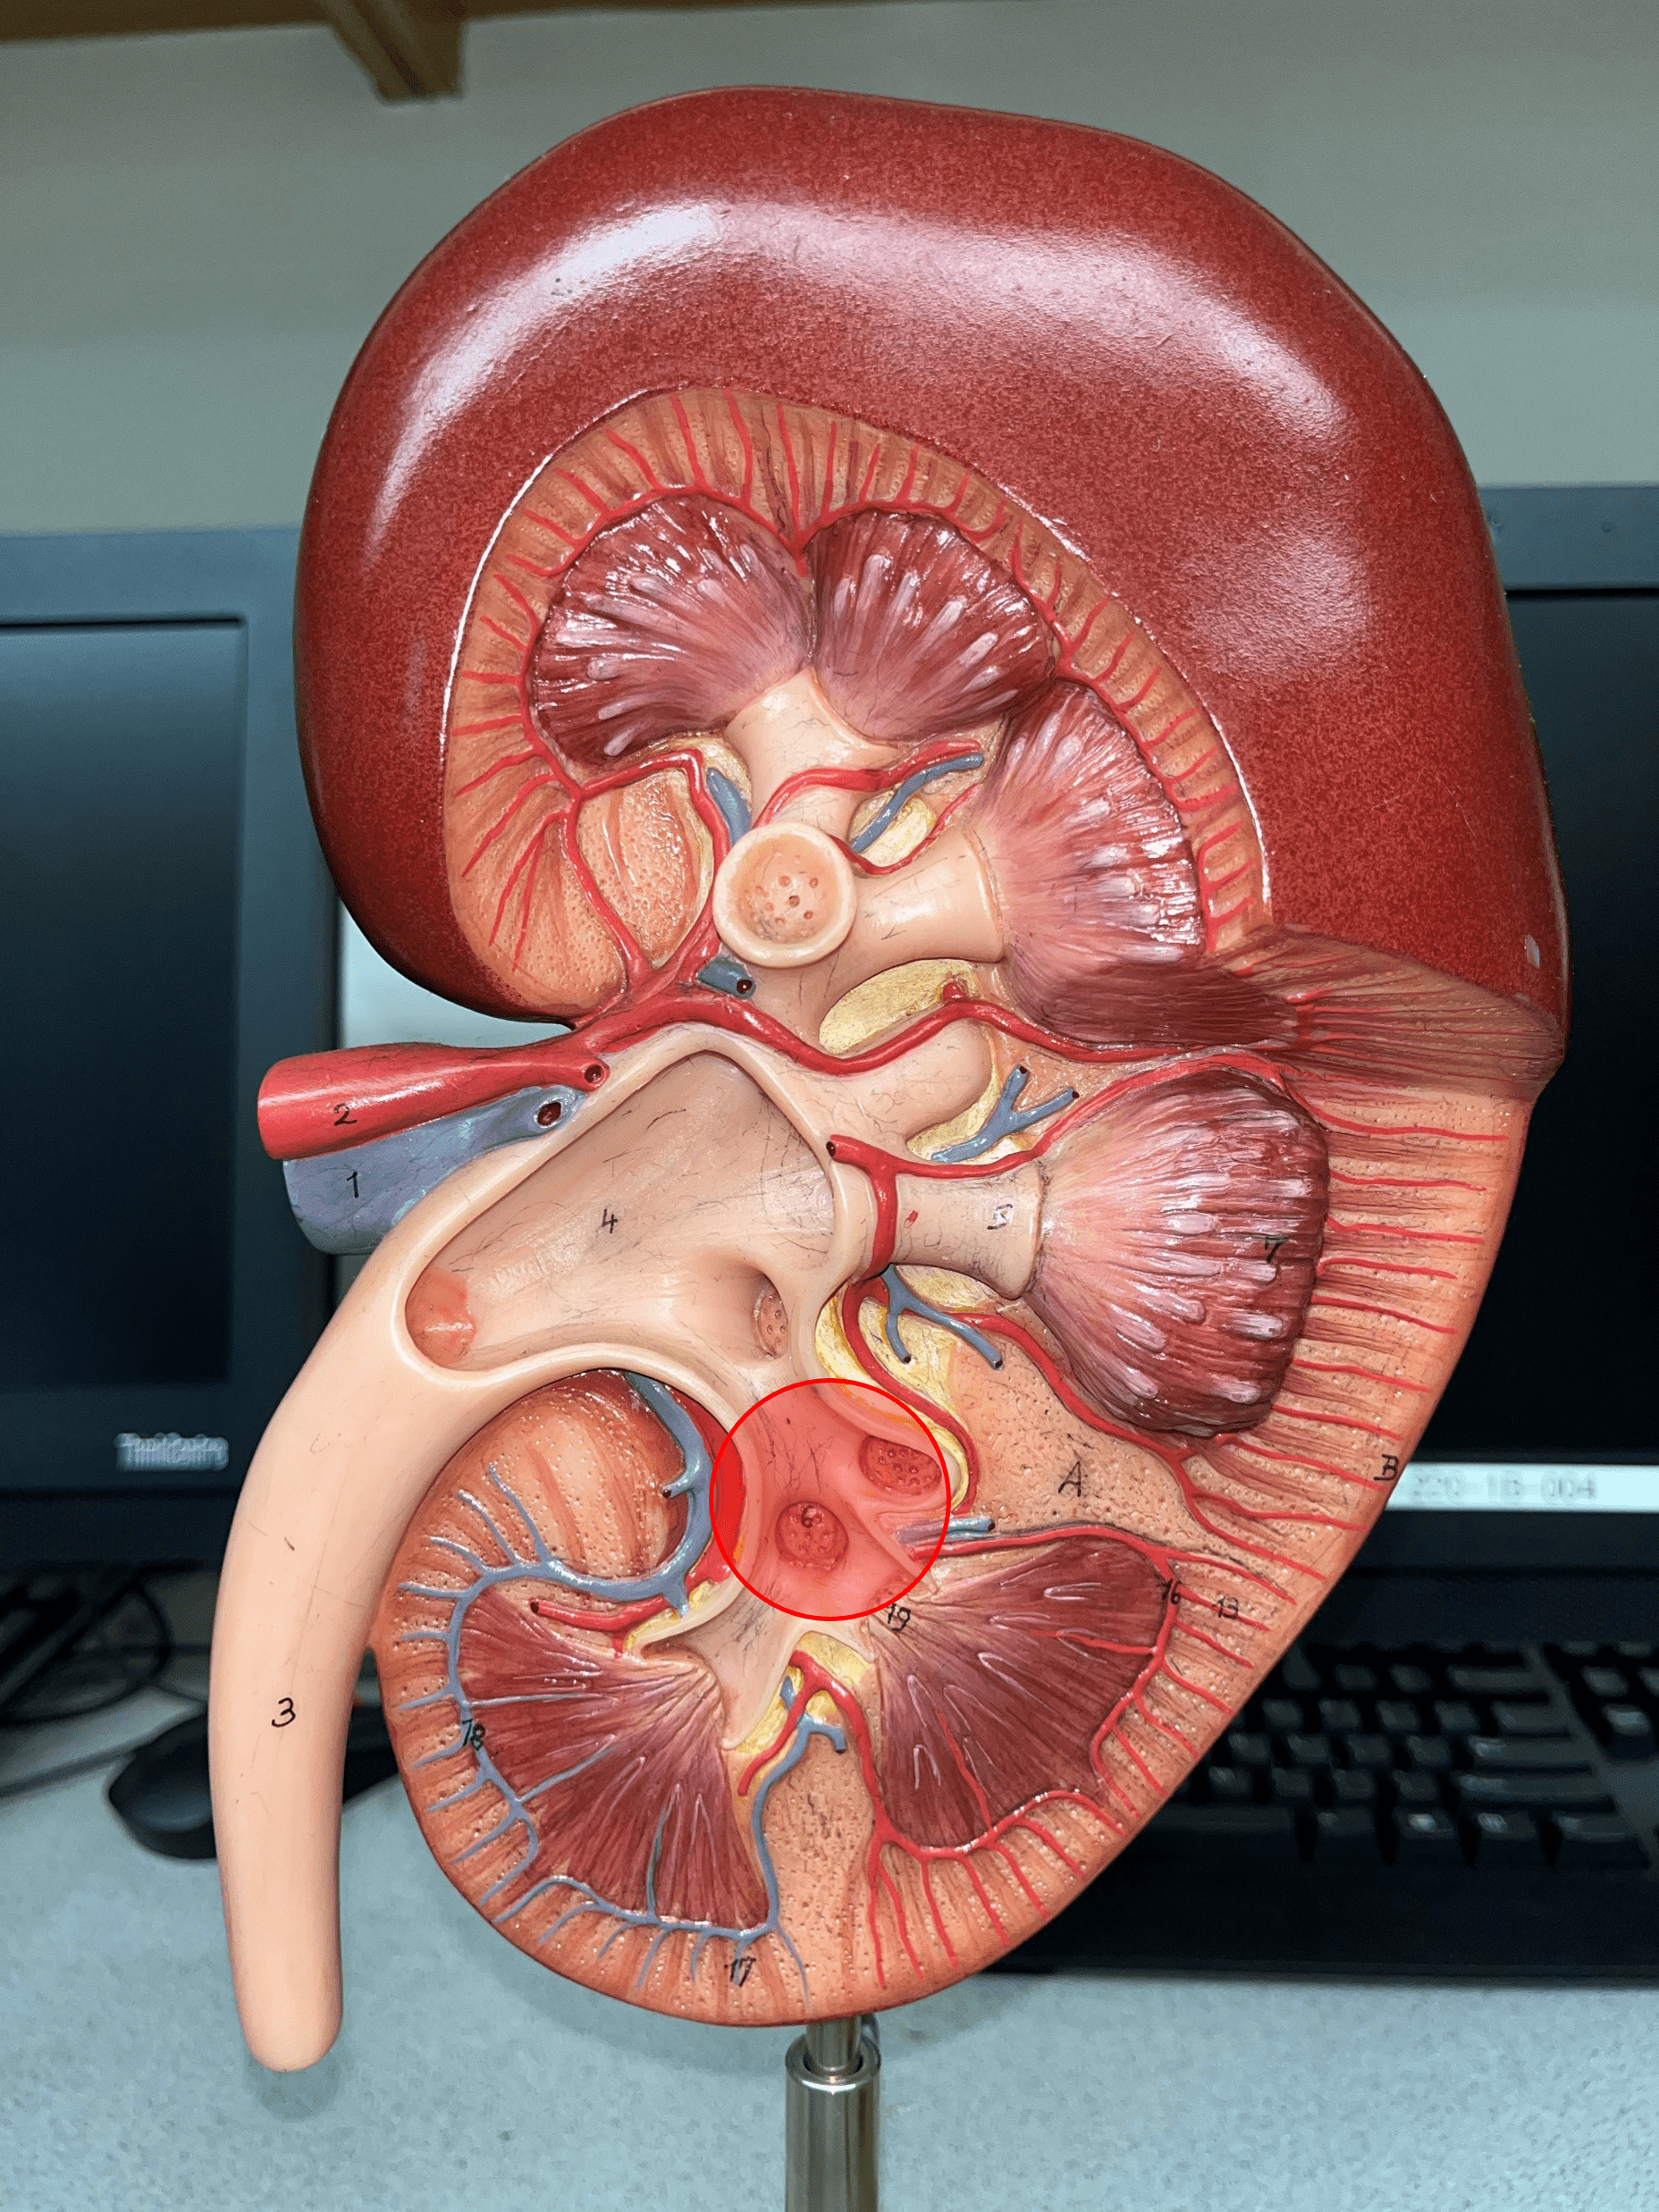

interlobar vein

• Extends between the renal pyramids.

• The convergence of arcuate vv.

• Converges into the renal vein.

• The convergence of arcuate vv.

• Converges into the renal vein.